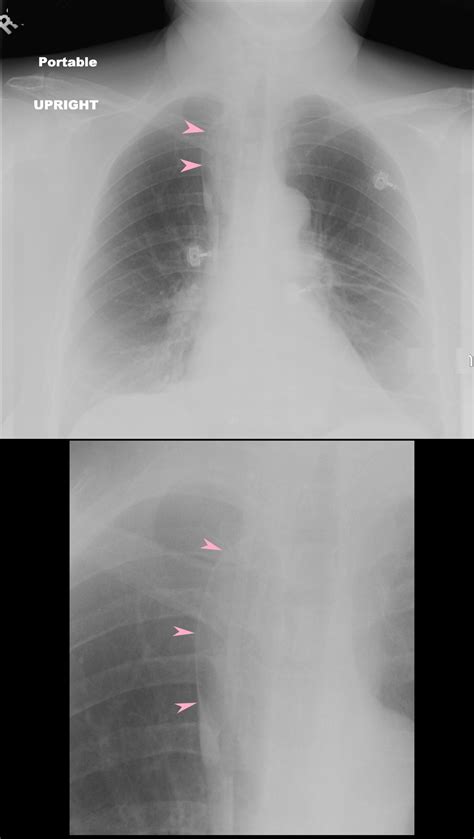

The hallmark of the Vena Azygos Lobe on a chest radiograph is a characteristic curvilinear density. Because of its unique formation, it is easily identifiable if one knows what to look for. Clinicians and radiologists typically identify the following features:

• The Azygos Fissure Line: A thin, convex line extending from the apex of the right lung toward the hilum.

• The Azygos Point (or Teardrop): A dense, teardrop-shaped opacity at the inferior end of the fissure line. This represents the cross-section of the misplaced azygos vein itself.

• Location: Always found in the right upper lobe.

While standard chest X-rays are usually sufficient for diagnosis, computed tomography (CT) provides a definitive view. On a CT scan, the Vena Azygos Lobe is clearly demonstrated as an isolated pleural-lined segment of lung tissue separated from the rest of the right upper lobe by the azygos fissure.